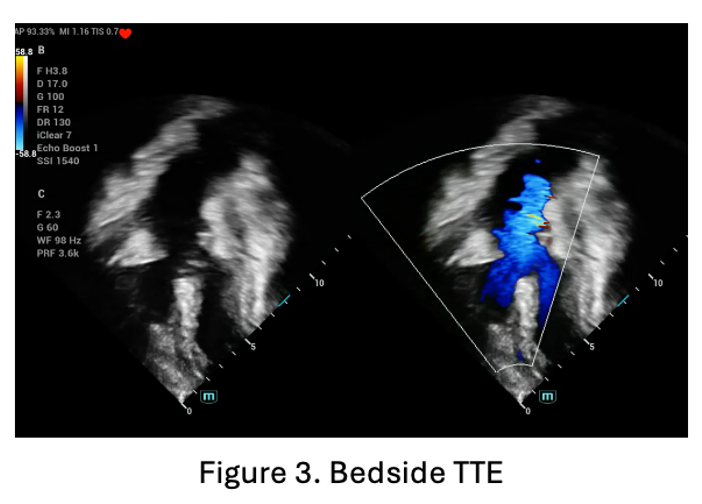

The patient came with lethargic, normal blood pressure and heart rate, increased work of breathing and decreased oxygen saturation into 62% on room air. Laboratory test showed increased hemoglobin and hematocrit into 21.7 mg/dL and 71.3% respectively. Bedside transthoracic echocardiography showed subaortic ventricular septal defect diameter 15-16 mm, right to left shunt, severe narrowing infundibulum, right ventricular outflow tract obstruction, with critical pulmonary stenosis.